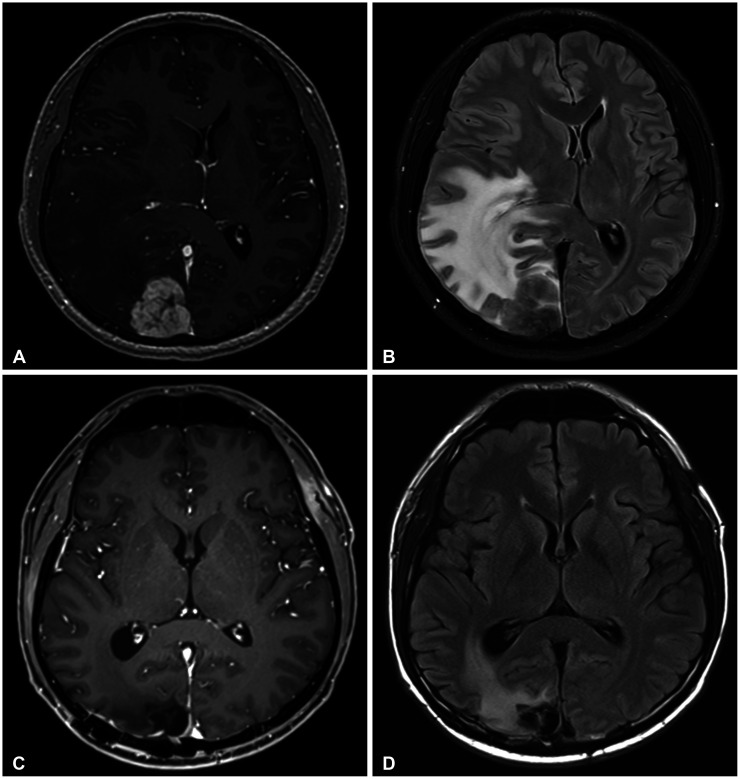

{"title":"Intracranial Involvement of Systemic Hodgkin Lymphoma: A Case Report and Literature Review.","authors":"Hwanhee Lee, Sangjun Ahn, Seung Heon Cha, Won Ho Cho","doi":"10.14791/btrt.2023.0041","DOIUrl":null,"url":null,"abstract":"<p><p>A 27-year-old male patient, previously diagnosed with Hodgkin lymphoma (HL), presented with gait disturbance. Brain MRI showed a 4.5 cm mass lesion in the right occipital lobe, suggesting either intracranial involvement of HL or a potential meningioma. Despite high-dose methotrexate and steroid treatment, the patient's symptoms persisted, and imaging showed an enlarging mass, leading to surgical intervention. Histopathological examination confirmed central nervous system (CNS) involvement of HL. Postoperatively, the patient underwent whole-brain radiotherapy and demonstrated marked clinical improvement. Our literature review from 1980 to 2023 identified only 46 cases of intracranial HL (IC-HL), underscoring its rarity. Lymphomas represent 2.2% of brain tumors, with 90%-95% being diffuse large B-cell lymphoma (DLBCL). In contrast, the incidence of CNS-HL patients is a mere 0.02%. Notably, IC-HL and intracranial DLBCL have differences in their typical locations and treatment strategies. Unlike DLBCL, which predominantly appears in the supratentorial region (87%), IC-HL is found there in 61.5% of cases. Additionally, 33.3% of IC-HL cases occur in the cerebellum, with 43.5% associated with posterior circulation regions. Furthermore, while biopsy followed by chemotherapy induction is a common strategy for DLBCL, 81.8% of IC-HL cases underwent surgical resection, and only 18.1% had a biopsy alone. The distinct characteristics of IC-HL tumors, including their larger size, attachment to the dura, and fibrotic nature with clear boundaries, might account for the preference for surgical intervention. The unique features of IC-HL compared to DLBCL highlight the need for distinct considerations in diagnosis and management.</p>","PeriodicalId":72453,"journal":{"name":"Brain tumor research and treatment","volume":"12 1","pages":"63-69"},"PeriodicalIF":0.0000,"publicationDate":"2024-01-01","publicationTypes":"Journal Article","fieldsOfStudy":null,"isOpenAccess":false,"openAccessPdf":"https://www.ncbi.nlm.nih.gov/pmc/articles/PMC10864131/pdf/","citationCount":"0","resultStr":null,"platform":"Semanticscholar","paperid":null,"PeriodicalName":"Brain tumor research and treatment","FirstCategoryId":"1085","ListUrlMain":"https://doi.org/10.14791/btrt.2023.0041","RegionNum":0,"RegionCategory":null,"ArticlePicture":[],"TitleCN":null,"AbstractTextCN":null,"PMCID":null,"EPubDate":"","PubModel":"","JCR":"","JCRName":"","Score":null,"Total":0}

A 27-year-old male patient, previously diagnosed with Hodgkin lymphoma (HL), presented with gait disturbance. Brain MRI showed a 4.5 cm mass lesion in the right occipital lobe, suggesting either intracranial involvement of HL or a potential meningioma. Despite high-dose methotrexate and steroid treatment, the patient's symptoms persisted, and imaging showed an enlarging mass, leading to surgical intervention. Histopathological examination confirmed central nervous system (CNS) involvement of HL. Postoperatively, the patient underwent whole-brain radiotherapy and demonstrated marked clinical improvement. Our literature review from 1980 to 2023 identified only 46 cases of intracranial HL (IC-HL), underscoring its rarity. Lymphomas represent 2.2% of brain tumors, with 90%-95% being diffuse large B-cell lymphoma (DLBCL). In contrast, the incidence of CNS-HL patients is a mere 0.02%. Notably, IC-HL and intracranial DLBCL have differences in their typical locations and treatment strategies. Unlike DLBCL, which predominantly appears in the supratentorial region (87%), IC-HL is found there in 61.5% of cases. Additionally, 33.3% of IC-HL cases occur in the cerebellum, with 43.5% associated with posterior circulation regions. Furthermore, while biopsy followed by chemotherapy induction is a common strategy for DLBCL, 81.8% of IC-HL cases underwent surgical resection, and only 18.1% had a biopsy alone. The distinct characteristics of IC-HL tumors, including their larger size, attachment to the dura, and fibrotic nature with clear boundaries, might account for the preference for surgical intervention. The unique features of IC-HL compared to DLBCL highlight the need for distinct considerations in diagnosis and management.